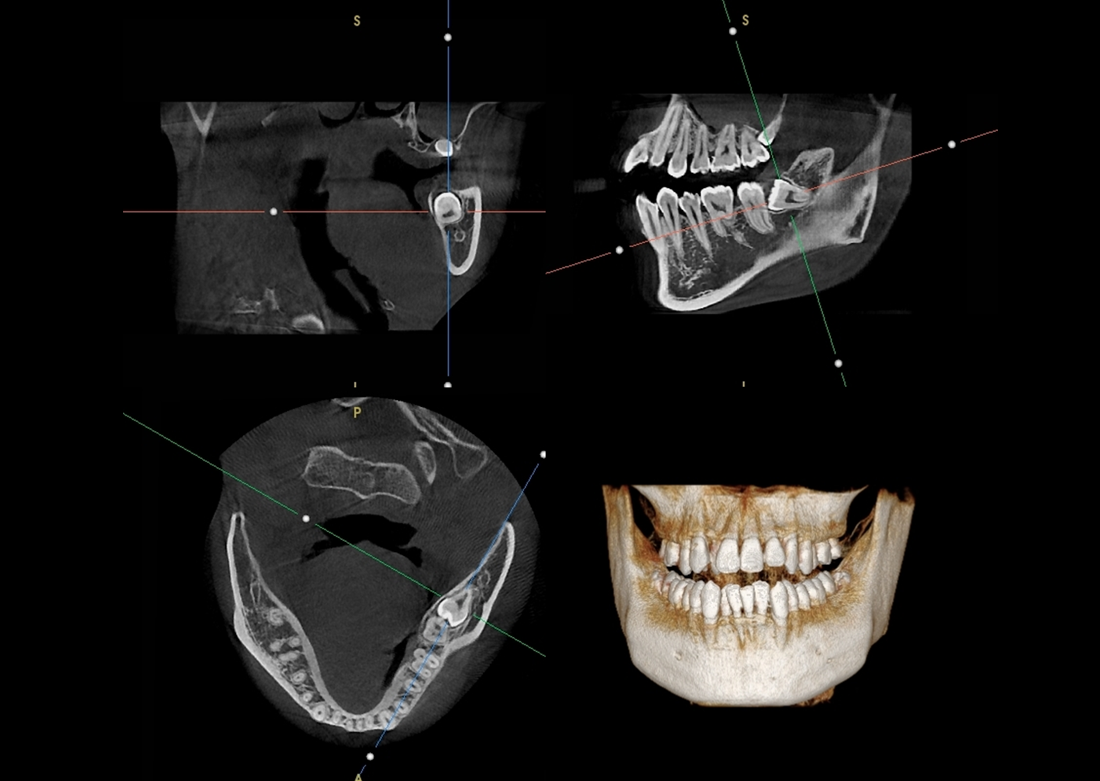

The Papaya 3D Premium/Ultra is the newest generation in a long line of Genoray products designed to produce accurate diagnostic images with wider treatment applications including implants, endo, ortho, airway, TMJ, and orthognathic surgeries. Optimized acquisition PC/Monitor/Accessories, model scan/STL converter, and perpetually licensed software suites included.

- Papaya 3D Premium CBCT: Min 4x5 to Max 16x14 FOV

- Papaya 3D Ultra CBCT: Min 4x5 to Max 23x24* FOV

*Papaya 3D Ultra comes supplied with free Invivo software, enabling CT extrapolated cephalometric images.